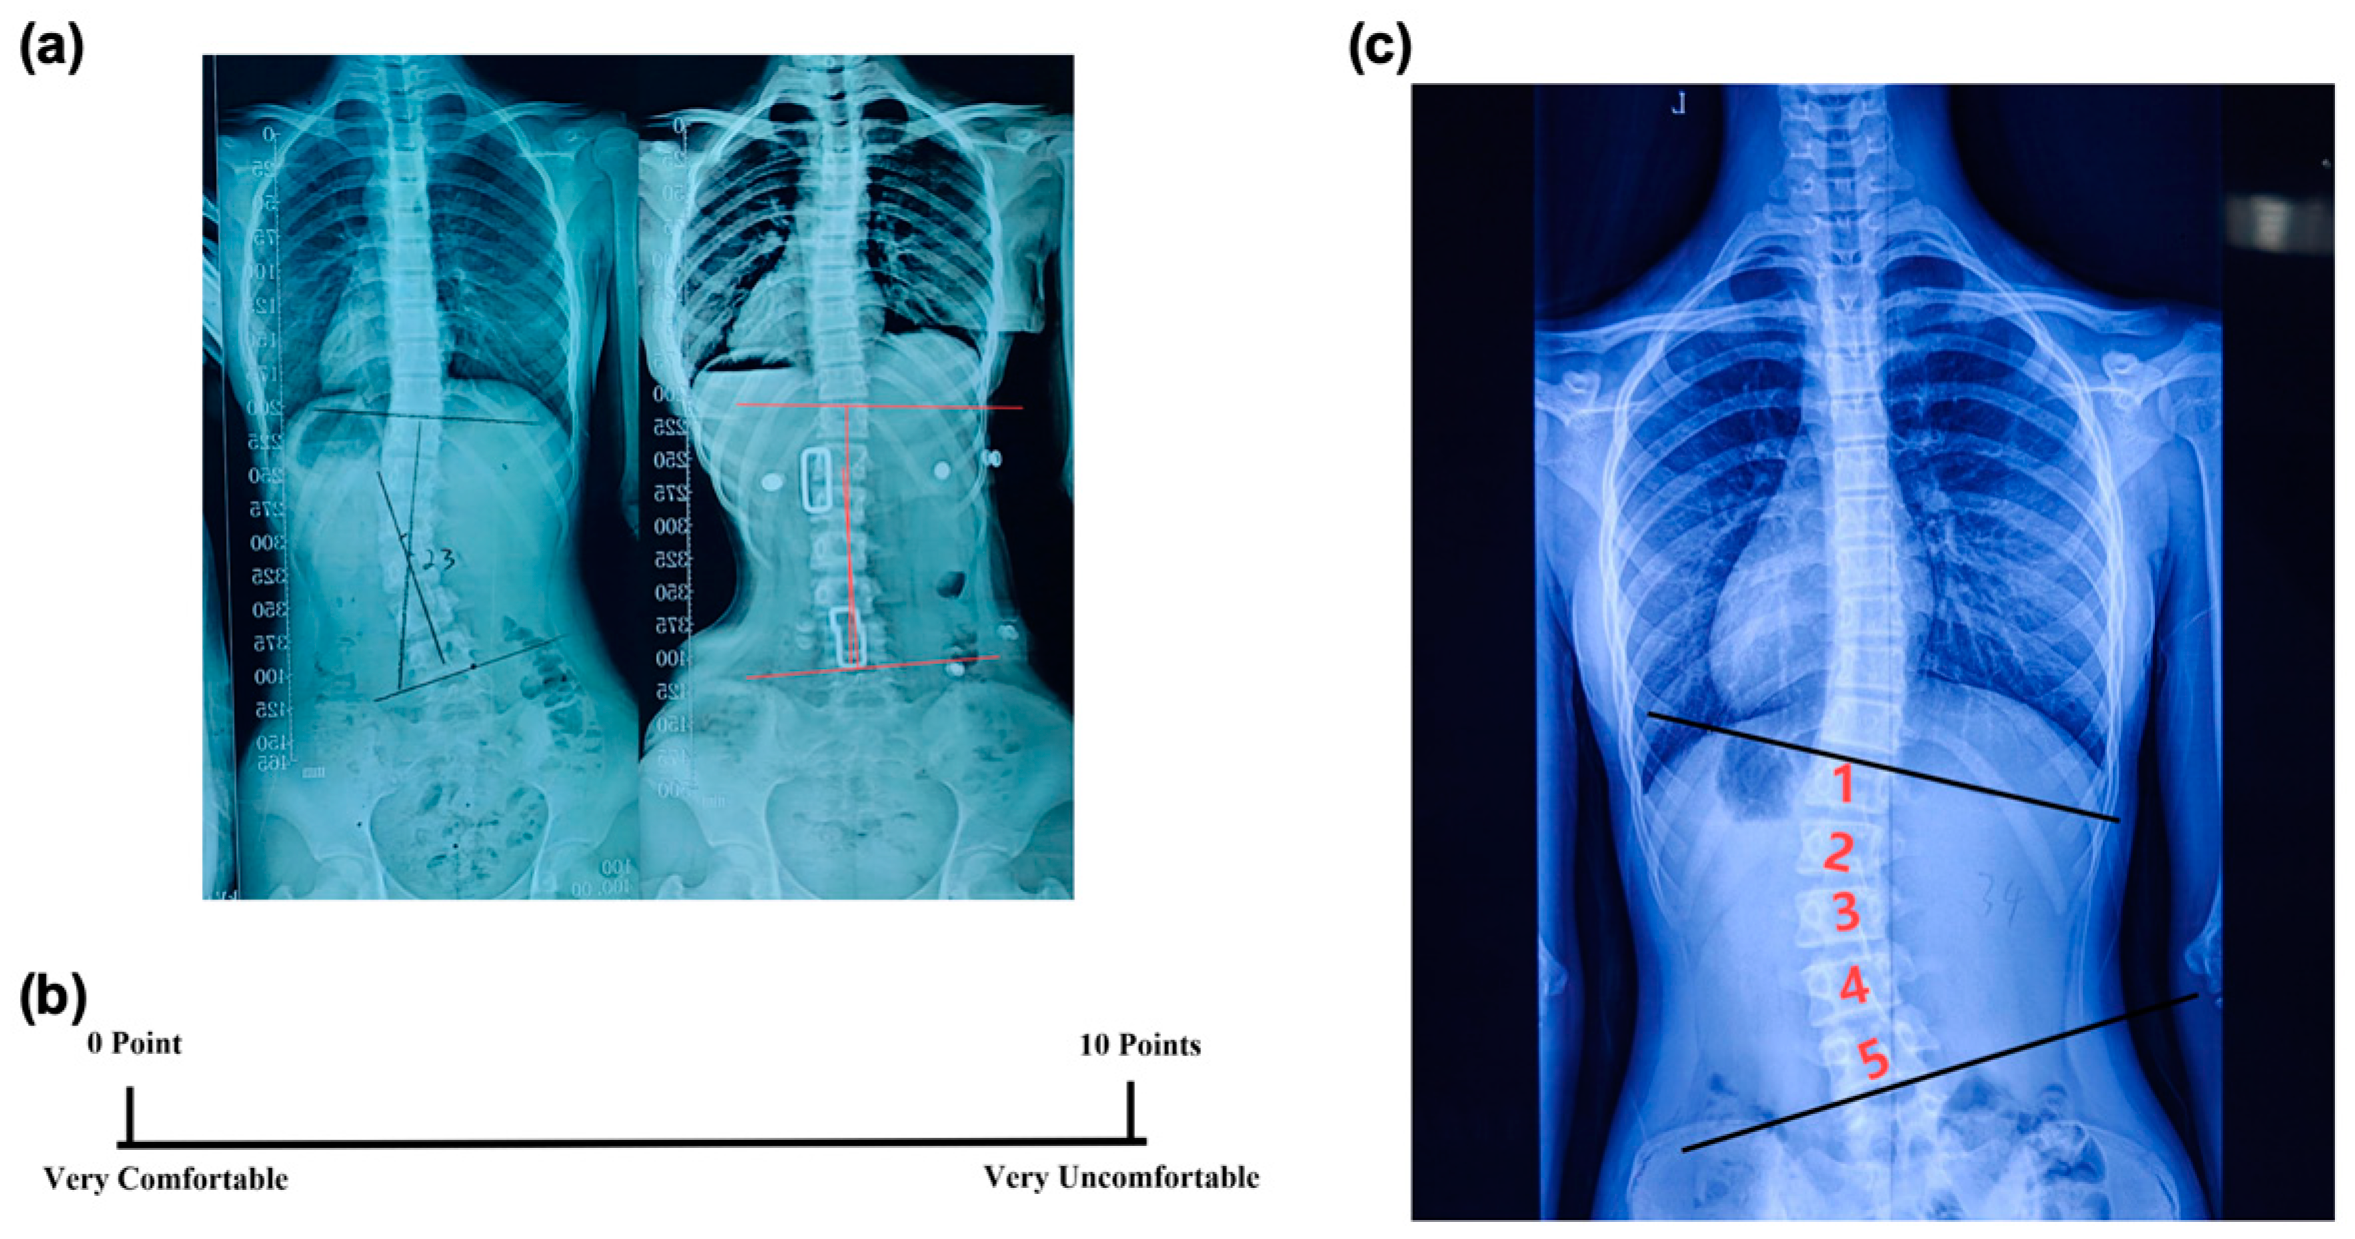

- In-brace Correction Ratio: Immediately after the patients wore the spinal braces, an X-ray examination was conducted to measure the in-brace Cobb angle (Figure 3a). The in-brace correction ratio was calculated using the following equation:

- Visual Analogue Scale (VAS): After fitting the brace, the VAS was used to assess a subject’s comfort level [20]. The scale ranged from 0 to 10, with 0 meaning very comfortable and 10 meaning very uncomfortable (Figure 3b). This rating was given independently by the patient to ensure an unbiased assessment of their comfort level while wearing the brace.